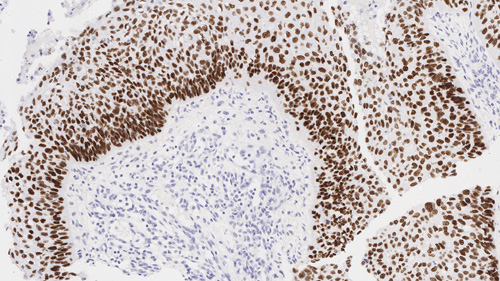

Squamous cell carcinoma of lung: Immunohistochemistry staining of p40. p40: clone BC28

p40 (Delta Np63) é um produto truncado do p63. É normalmente expresso na camada celular basal ou progenitora de células basais, do epitélio estratificado da próstata, bem como células mioepiteliais da mama e glândulas salivares, e citotrofoblastos na placenta, e apresenta um padrão de coloração nuclear com IHC. Entre os inúmeros neoplasmas com resultados positivos para p40, carcinomas de células escamosas de origem pulmonar e não pulmonar podem ser identificados a partir de outras malignidades.